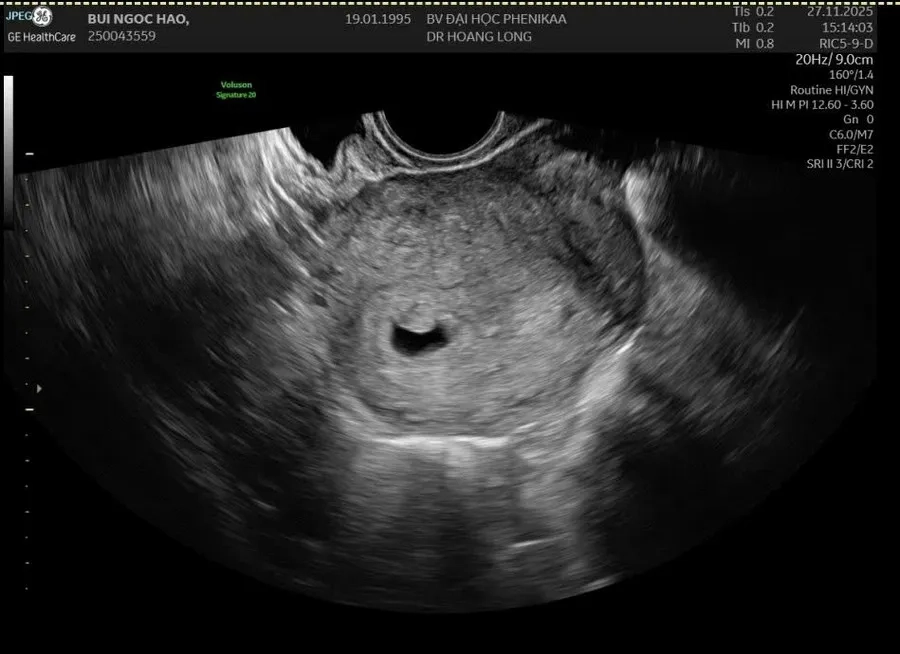

Tim thai thường được phát hiện qua siêu âm, khi túi thai đạt kích thước khoảng 18 – 20mm, tương ứng với giai đoạn từ tuần thai thứ 6 đến tuần thứ 7. Tuy nhiên, thời điểm nghe được tim thai có thể khác nhau tùy thuộc vào từng trường hợp mang thai.

Ở tuần thứ 6 – 7, bác sĩ thường sử dụng thiết bị siêu âm Doppler cầm tay áp lên bụng thai phụ để khuếch đại và ghi lại âm thanh của tim thai. Đây là một bước quan trọng để đánh giá sự phát triển của thai nhi.

Một điểm quan trọng mẹ cần biết: siêu âm đầu dò âm đạo (transvaginal ultrasound) có thể phát hiện tim thai sớm hơn siêu âm qua thành bụng - đặc biệt khi túi thai còn nhỏ dưới 18mm. Đây là lý do bác sĩ đôi khi chỉ định thay đổi phương pháp siêu âm nếu chưa nghe được tim thai ở tuần 6. Nhịp tim thai bình thường trong giai đoạn này dao động từ 120–160 lần/phút.

Trong một số trường hợp, nếu không nghe được tim thai, nguyên nhân có thể do thai còn nhỏ hoặc thiết bị siêu âm không đủ nhạy. Khi đó, bác sĩ sẽ khuyến nghị mẹ kiểm tra lại sau khoảng một tuần. Điều này giúp đảm bảo kết quả chính xác hơn và loại trừ các vấn đề sức khỏe nghiêm trọng có thể ảnh hưởng đến thai nhi.

Tim thai thường xuất hiện khi túi thai đạt 18 – 20mm nhưng thời gian phát hiện có thể khác nhau ở mỗi trường hợp